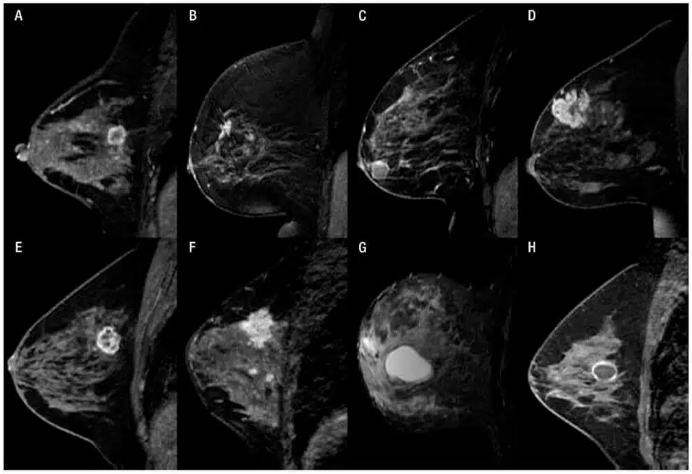

Mamografia, ultrassom e ressonância — quando cada exame é indicado e qual a relação custo-benefício.